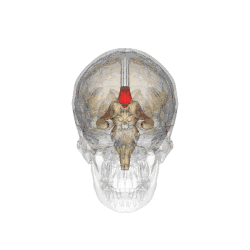

Corpus callosum from above, front part at the top of the image

Sagittal section of a brain, front part to the left. The corpus callosum can be seen in the center, in light gray